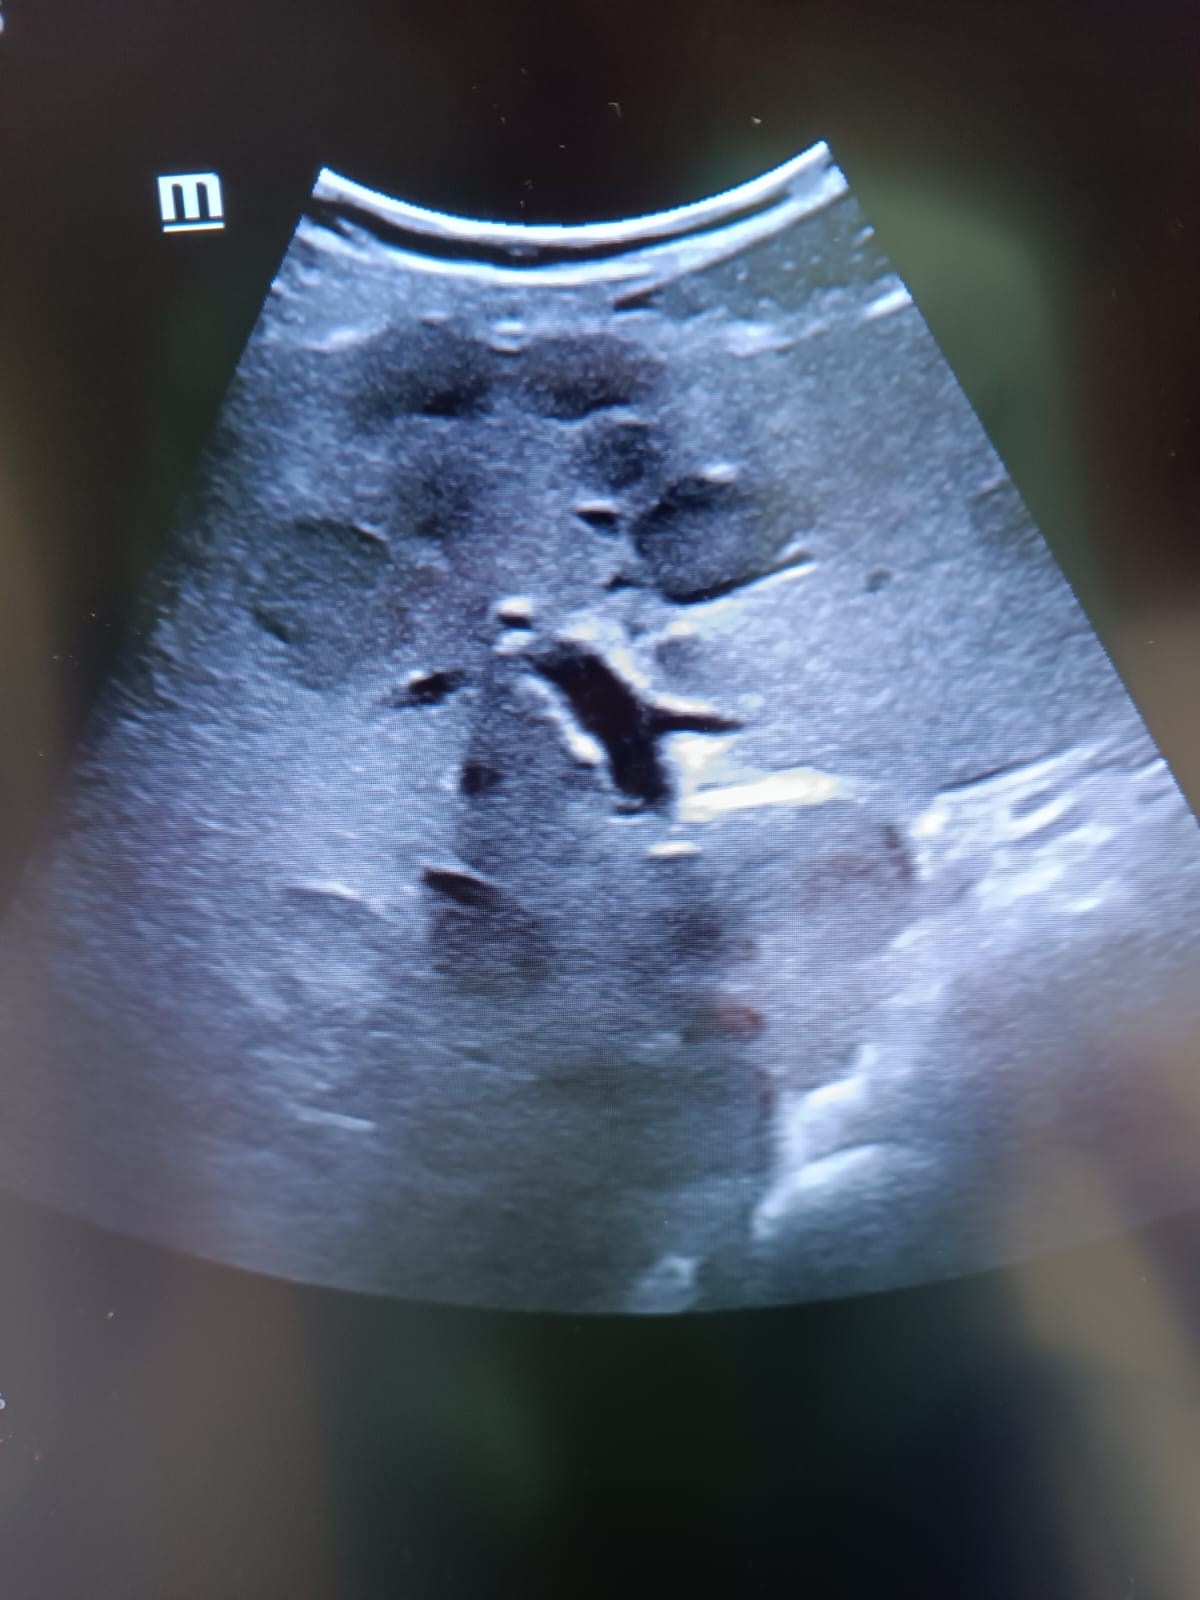

Hallazgos ecográficos

Por sindrome constitucional, hepatomegalia y antecedente de alcoholismo, se decide la realización de ecografía abdominal clínica en consulta. Esta revela múltiples lesiones hepáticas de características ocupantes de espacio, con un patrón irregular sugestivo de metástasis, vias intra y extrahepáticas biliares normales. Este hallazgo refuerza la sospecha clínica de neoplasia avanzada y facilita la derivación a consultas de alta resolución con la priorización de un TAC toracoabdominal preferente.